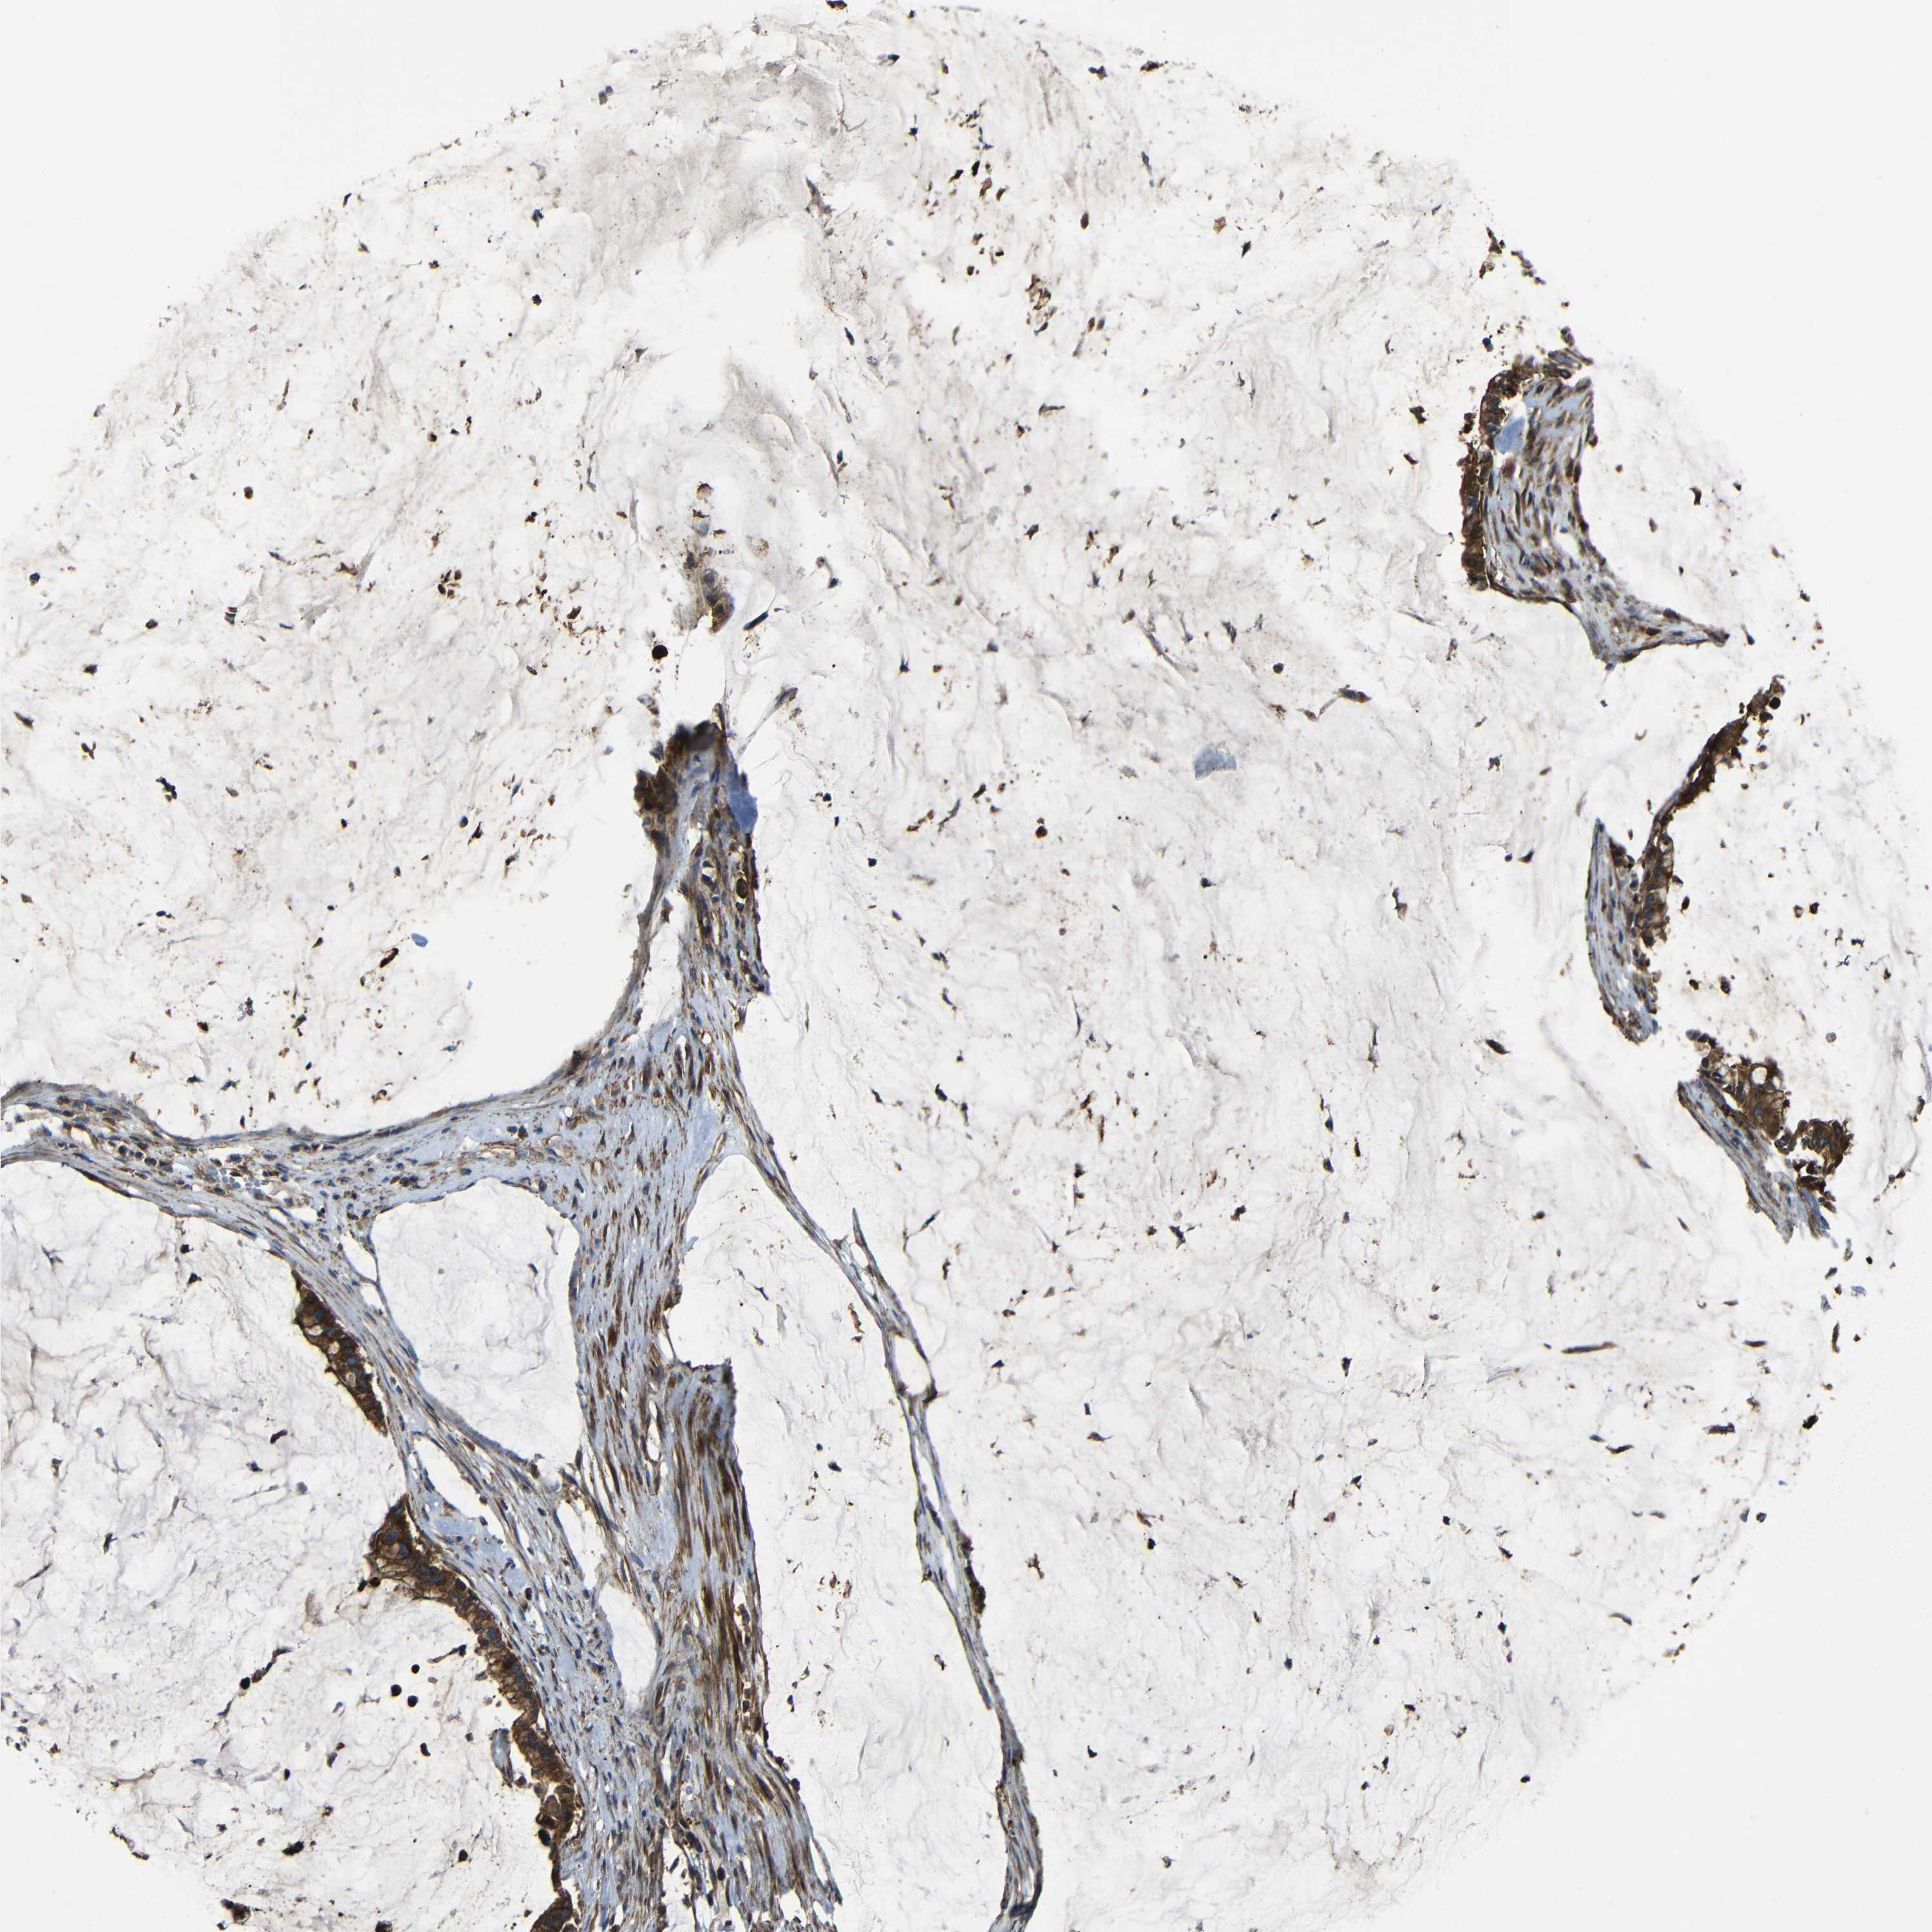

PANCREATIC CANCER - Protein expressioni

A mouse-over function shows sample information and annotation data. Click on an image to view it in a full screen mode. Samples can be filtered based on level of antibody staining by selecting one or several of the following categories: high, medium, low and not detected. The assay and annotation is described here.

Note that samples used for immunohistochemistry by the Human Protein Atlas do not correspond to samples in the TCGA dataset.

Antibody stainingi

Antibody staining in the annotated cell types in the current human tissue is reported as not detected, low, medium, or high, based on conventional immunohistochemistry profiling in selected tissues. This score is based on the combination of the staining intensity and fraction of stained cells.

Each image is clickable and will lead to virtual microscopy that enables deeper exploration of all samples and also displays staining intensity scores, fraction scores and subcellular localization as well as patient and tissue information for each sample.

Antibody CAB013717

Staining

High

Medium

Low

Not detected

Intensity

Strong

Moderate

Weak

Negative

Quantity

>75%

75%-25%

<25%

None

Location

Nuclear

Cytoplasmic/membranous

Cytoplasmic/membranous,nuclear

Adenocarcinoma, NOS